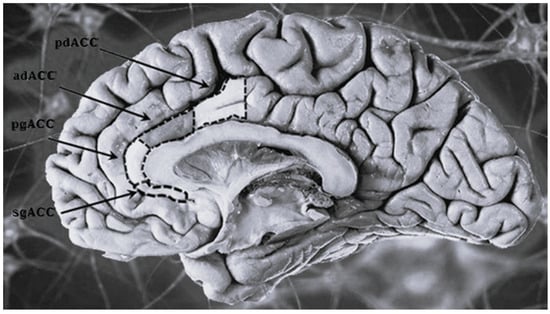

| Anterior cingulate cortex (ACC) | The most distal portion of the cingulate gyrus (bilateral structure surrounding the corpus callosum). Given the direct connections it establishes with the prefrontal cortex and some limbic structures (amygdala, hypothalamus, and hippocampus) it participates in the encoding of emotions particularly anxiety, anger and fear. Also it regulates some endocrine and vegetative functions and participates in emotional language production. | Regardless of the subtype it has been documented the existence of a general volumetric reduction of the ACC, localized in particular in its subgenual portion (sgACC), more evident in patients with affective and/or depressive comorbidity. No significant age- or subtype- related differences have been reported between patients. |

| Anterior cingulate | The volume appears moderately reduced, generating a greater impairment of functions such as emotional processing and the management of fear and frustration. | The volume is reduced but significantly less than the DB-1. |